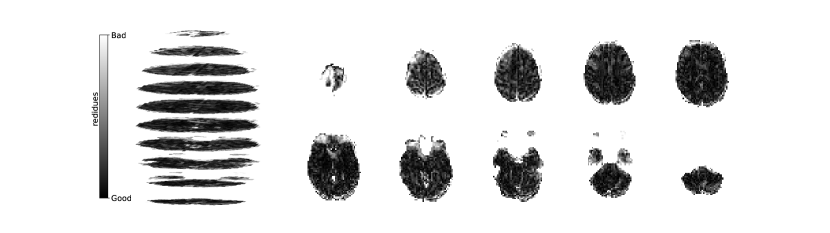

Figure 2 illustrates the distribution of residues (observed vs. estimated differences) on the fMRI volumes for the NODDI dataset. Clearly, by visual inspection, (iv) model has the darker and biggest area of shaded regions, which implies a better coverage across the brain regions and better synthesis quality. Models with topographical attention, (ii) and (iv), corresponding to Figures 2(b) and 2(d), respectively, significantly improve the synthesis, as shown by the darker and bigger areas against (i) and (iii) depicted in Figures 2(a) and 2(c), respectively. Particularly, we notice that models (i) and (iii) report difficulty in the retrieval of haemodynamical activity located in occipital and parietal lobes.

To better address which regions our baselines had more difficulty retrieving, the normalized residues were computed and are illustrated in Figure 3. Baselines – corresponding to models (i) and (ii), shown in Figures 3(a) and 3(b) respectively, which correspondingly implement a linear projection in the latent space and topographical attention –, have difficulty retrieving the prefrontal, occipital and parietal lobes, as the shade tends to a lighter grey in that region. Model (iv), shown in Figure 3(d), does not show a noticeable region with a lighter tone of grey, which implies no evident difficulty in retrieving haemodynamical activity across the different brain regions.